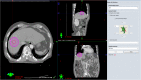

Objective: Stereotactic body radiation therapy (SBRT) for the treatment of a malignancy in the liver requires the perilesional implantation of fiducial markers for lesion detection. The purpose of this study is to evaluate the efficacy and safety of ultrasound (US) -guided marker implantation for SBRT.

Methods: We retrospectively reviewed 299, US-guided, intrahepatic fiducial markers implanted in 101 patients between November 2013 and September 2014. SBRT-planning CT images were analyzed to determine the technical success of the implantation, the mean distance between the tumor margin and the marker, with the ideal location of fiducials defined as the distance between a marker and a tumor less than 3 cm and the distance between markers greater than 2 cm according to the tumor conspicuity seen on gray-scale US and the artifact obscuring tumor margins. We also evaluated procedure-related major and minor complications.

Results: Technical success was achieved in 291 (97.3%) fiducial marker implantations. The mean distance between the tumor and the marker was 3.1 cm (S.D., 2.1 cm; range, 0-9.5 cm). Of 101 patients, 72 lesions (71.3%, 2.2 ± 1.0 cm; range, 0-3.0 cm) had fiducial markers located in an ideal location. The ideal location of fiducials was more common in visible lesions than in poorly conspicuous lesions (90.2% vs. 52.0%, P < 0.001). Seventeen markers (5.8%) developed beam-hardening artifacts obscuring the tumor margins. There were no major complications, although 12 patients (11.9%) developed minor complications.